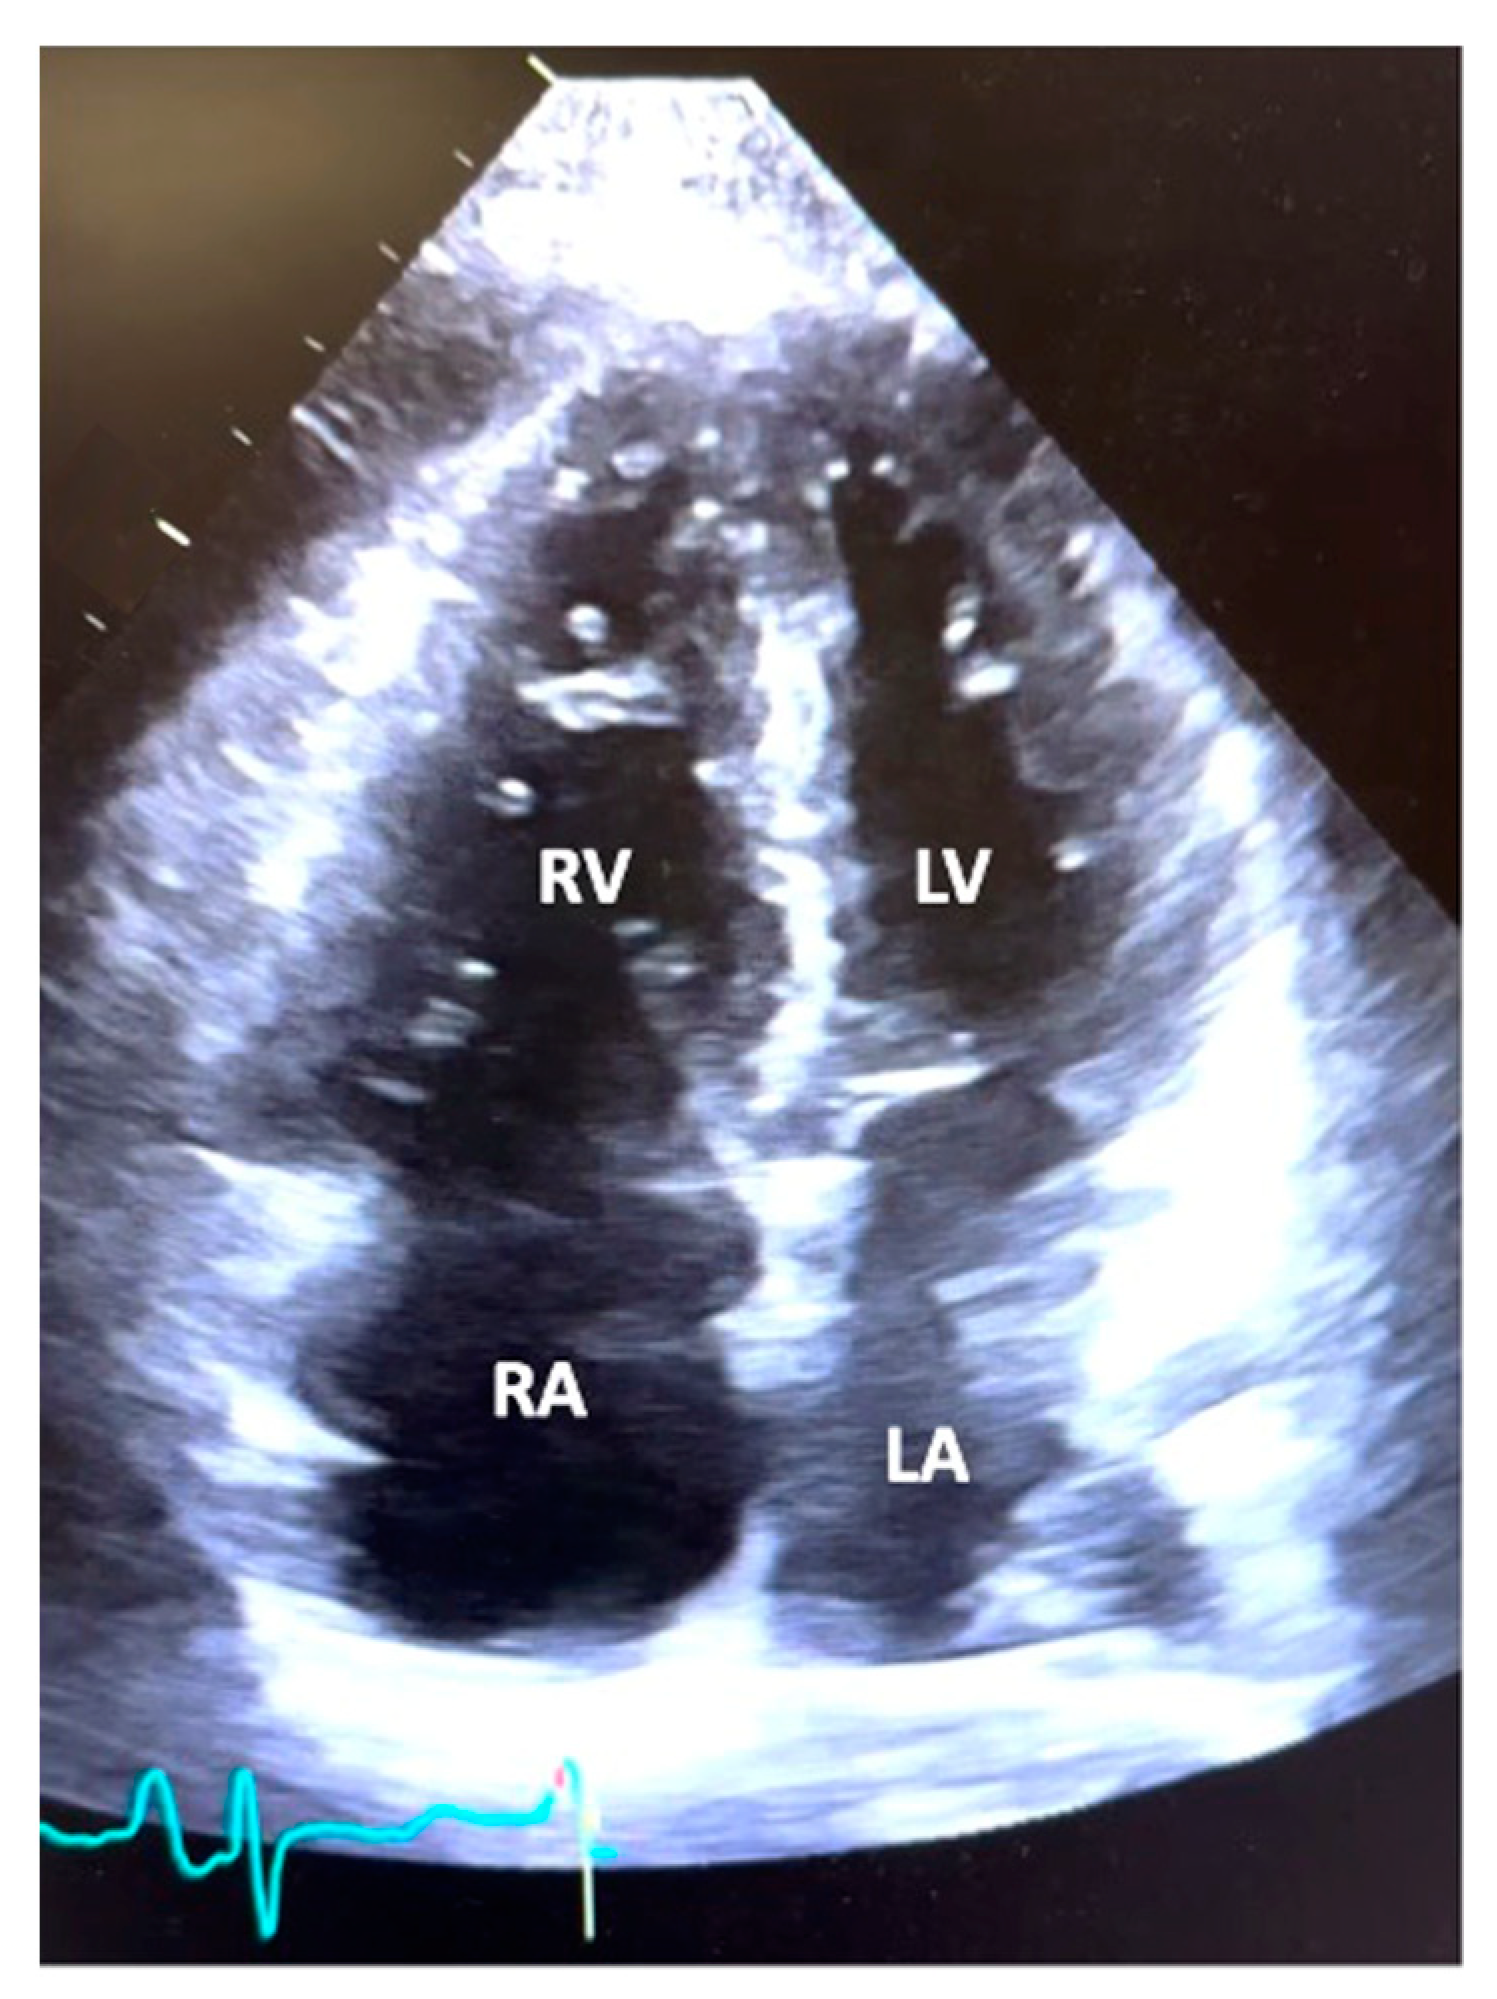

Table 3 and Table 4 summarize the echocardiographic and hemodynamic data from RHC, respectively. Echocardiography demonstrated normal left ventricular function, with a mean left ventricular EF of 60.9% ± 8.0 with a lack of left-sided valvular heart disease. The majority of patients had severe RV dilatation (66.1%) and severe RV systolic dysfunction (53.2%). The mean PA systolic pressure was 79.2 ± 22.2 mmHg, and the mean TAPSE was 1.4 ± 0.4 cm. RV outflow tract pulse wave Doppler systolic notching, a Doppler sign of elevated pulmonary vascular resistance and low pulmonary artery compliance, was present in 67.7%, absent in 19.4%, and not evaluated in 12.9% of patients. The degree of ventricular septal flattening was noted to be severe in 46.8%, moderate in 37.1%, mild in 9.7%, and absent in 6.4% of the patient population. Tricuspid regurgitation was noted to be either moderate or severe in 79.1% of subjects. Pericardial effusion was noted to be present in 46.8% of patients and mild to moderate in 90% of patients. Thus, on average, subjects had moderate to severe RV dysfunction, ventricular septal flattening, and tricuspid regurgitation. A representative image of the typical apical four-chamber view from a patient in the study is depicted in Figure 1.

Figure 1.

Echocardiogram. A representative image of an apical four-chamber view from a patient in the study demonstrating moderate right ventricular (RV) dilation, right atrial (RA) dilation, and normal left ventricular (LV) and left atrial (LA) size.